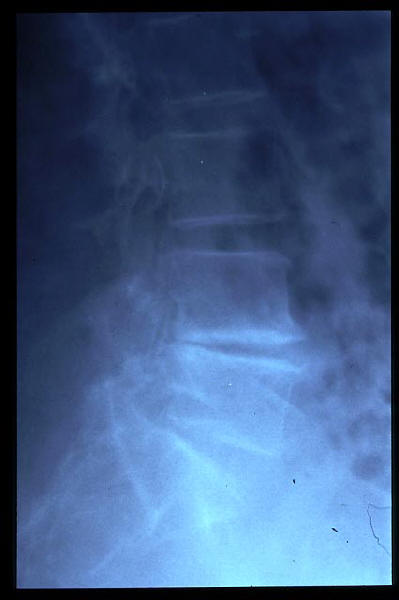

Osteoporosis. Cifosis.

Escoliosis, artrosis, aplastamiento...

Aplastamiento vertebral. Gas. Osteoporosis.

Aplastamiento vertebral. Osteoporosis.